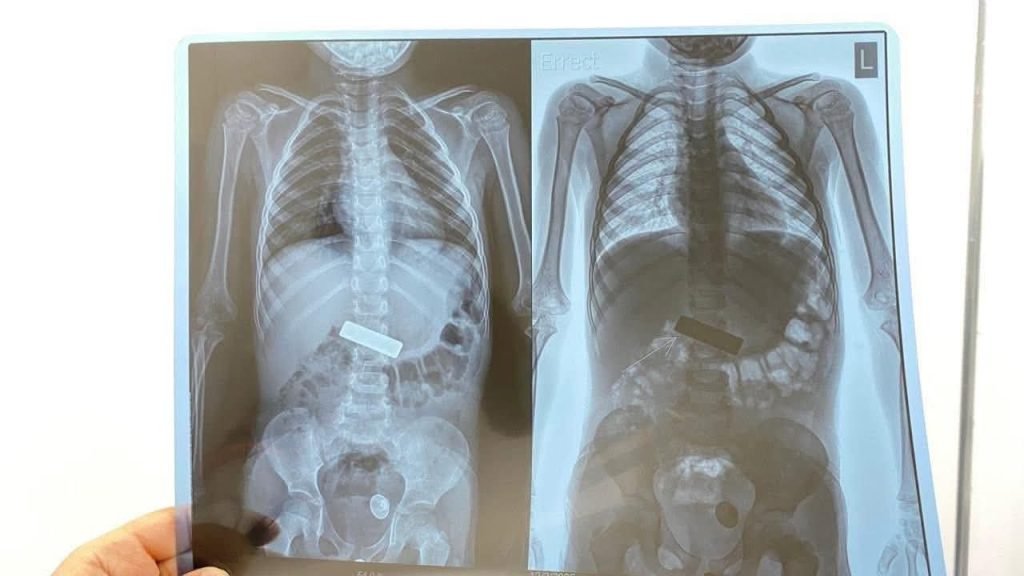

وقالت ادارة المستشفى أن “فريقا طبيا في مستشفى الجهاز الهضمي والكبد في النجف استقبل طفلة بحالة حرجة مع تدهور سريع في علاماتها الحيوية، وأظهرت الفحوصات وجود جسم معدني حاد عالق في المريء”.

واضاف، انه “تم إدخالها فورا إلى صالة العمليات وإجراء عملية ناظورية تحت التخدير العام، حيث جرى استخراج القطعة المعدنية بنجاح ،وغادرت المستشفى بصحة جيدة بفضل جهود الملاكات الطبية والتمريضية والصحية وكادر”.